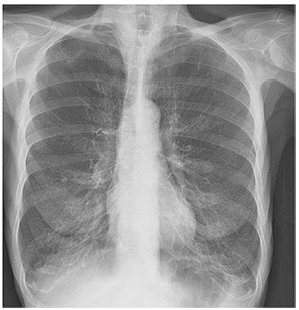

Os resultados de exames complementares feitos no dia da consulta revelam: creatinina de 0,7, ureia de 30, leucócito de 5.000, sem distúrbios hidroeletrolíticos, com PCR de 40. A imagem da radiografia de tórax é mostrada a seguir.